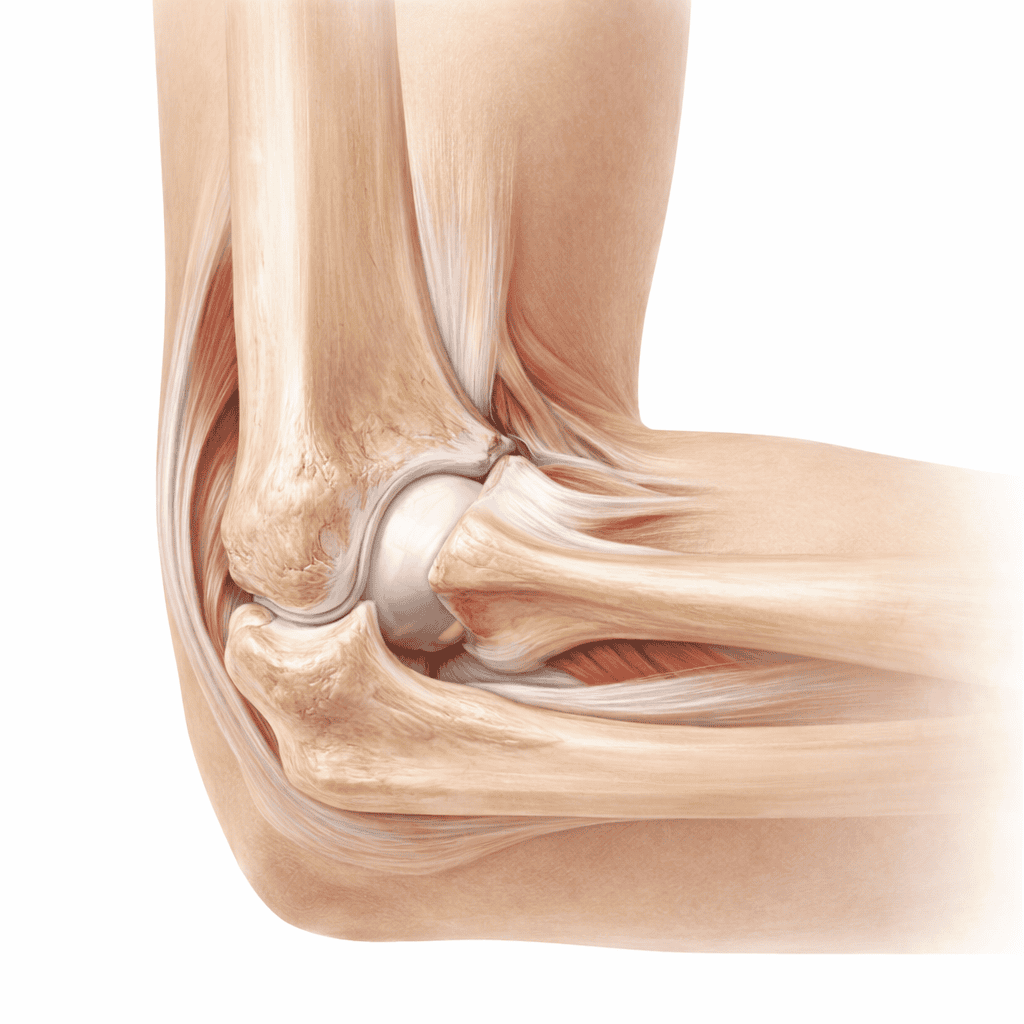

Cotul este format din trei oase — humerus, radius și ulnă — articulate între ele prin trei articulații distincte. Stabilitatea este asigurată de ligamentele colaterale medial și lateral, iar funcția de rotație a antebrațului depinde de articulația radio-ulnară proximală. Tendoanele extensorilor și flexorilor se inseră pe epicondilii humerali, făcând cotul vulnerabil la tendinopatii prin suprasolicitare. În plus, nervul cubital trece printr-un șanț îngust la nivelul cotului — compresia sa produce simptome neurologice caracteristice. Mai jos găsești cele mai frecvente afecțiuni ale cotului.

Structurile articulației cotului

Cotul reunește mobilitate și stabilitate prin structuri ligamentare, tendinoase și nervoase bine definite:

- Epicondilul lateral — inserția extensorilor mâinii și degetelor; sediul epicondilitei laterale („cotul tenismenului")

- Epicondilul medial — inserția flexorilor și pronatorilor; sediul epicondilitei mediale („cotul jucătorului de golf")

- Ligamentul colateral ulnar (LCU) — stabilizator principal al cotului la stres în valgus; frecvent lezat la aruncători

- Nervul cubital — trece prin șanțul epicondilului medial; compresia produce amorțeală în degetele IV–V (sindrom de tunel cubital)

- Bursa olecranului — localizată posterior; se inflamează în bursita olecranului

- Tendonul distal al bicepsului — se inseră pe tuberozitatea radială; poate fi rupt în traumatisme prin extensie bruscă